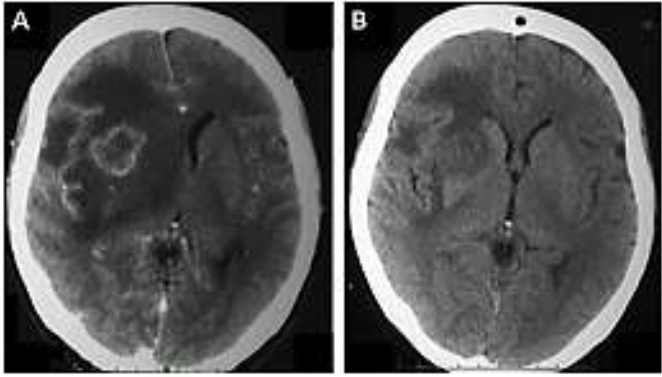

Paciente 44 anos, com perda de peso há 2 meses, em investigação de cefaleia, sonolência e crise convulsiva. Caso apresentasse essa imagem (imagem), assinale a alternativa que apresenta qual seria o diagnóstico e conduta adequadas.

Ressonância magnética de crânio